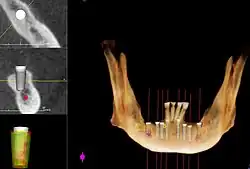

Методы, используемые для планирования имплантатов

Планирование

Общие соображения

При планировании зубных имплантатов основное внимание уделяется общему состоянию здоровья пациента, местному состоянию здоровья слизистых оболочек и челюстей, а также форме, размеру и положению костей челюстей, соседних и противолежащих зубов.